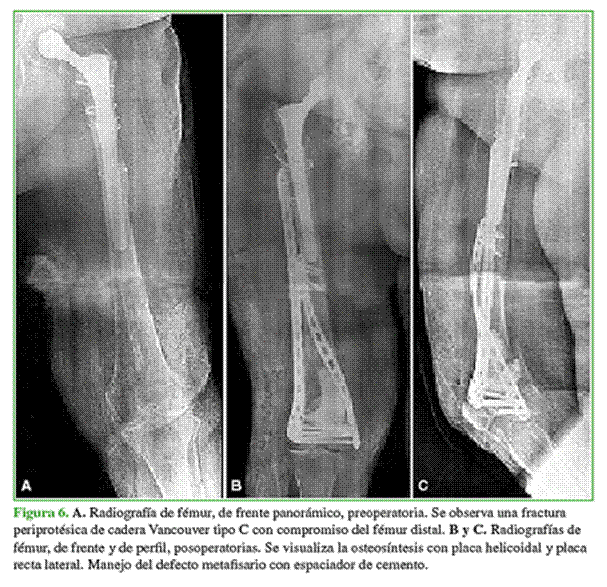

En todos los pacientes, se observó la consolidación radiográfica a los seis meses de la cirugía definitiva. Dos pacientes de la muestra tenían, en el momento de la osteosíntesis, defectos metafisarios que fueron resueltos con espaciadores de cemento y antibiótico, por lo que requirieron una nueva intervención con la colocación de injerto de banco. En estos casos, la carga se retrasó seis semanas, momento en el cual se realizó el segundo tiempo quirúrgico que consistió en el retiro del espaciador y el relleno del defecto con injerto óseo cadavérico. Nuevamente, se retrasó la carga seis semanas, y se logró la consolidación en ambos casos. En el resto de los pacientes, se inició un protocolo de carga progresiva que consistió en carga parcial por tres semanas y luego carga completa. Ninguno tuvo una lesión vasculonerviosa asociada (Figuras 3-6).

El puntaje promedio de dolor posoperatorio luego de la consolidación de la fractura fue 3. El paciente con cuadriplejia no fue evaluado en este aspecto (Tabla 2). El seguimiento radiográfico se realizó en el posoperatorio inmediato, a las 3 y 6 semanas, y a los 3, 6, 12, 18 y 24 meses. En la Tabla 3, se describen los resultados funcionales según el puntaje KOOS.6,7 La mediana de seguimiento fue de 24 meses (rango 6-36).

En un estudio biomecánico, Sezek y cols. compararon las placas rectas con las placas helicoidales colocadas por vía medial. Sostienen que la osteosíntesis recta convencional induce una protección indebida por tensión del hueso fracturado y puede causar algunos problemas de debilitamiento y aflojamiento del segmento. Otra desventaja es la falta de capacidad de torsión, lo que dificulta la colocación de la placa y puede determinar un grado de mala rotación de la fractura. Estos autores llegaron a la conclusión de que las placas helicoidales tienen mayor estabilidad ante la carga axial y las fuerzas torsionales en comparación con las placas rectas convencionales; sin embargo, las placas rectas tuvieron más resistencia a las fuerzas de flexión.8 Esto último probablemente se deba a que las placas helicoidales, al estar grifadas, son más débiles en los puntos donde se aplicó la fuerza.9 En nuestra serie, dos pacientes presentaron defectos metafisarios severos de fémur distal, por lo que el uso de doble osteosíntesis aumentó la rigidez del sistema, y les permitió a los pacientes la marcha con carga parcial inmediata luego de la cirugía definitiva y la carga completa a las seis semanas.